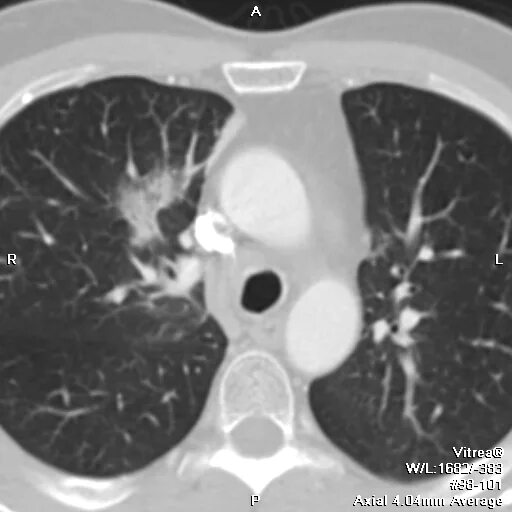

Метастазы в легких терапия